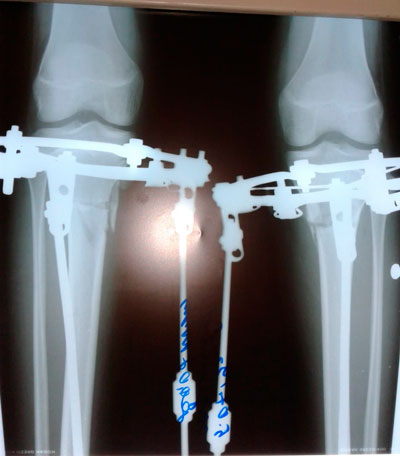

Дата операции - 15.06.2019г.

Дата снятия аппаратов - 20.08.2019.

Срок сращения - 65 дней.